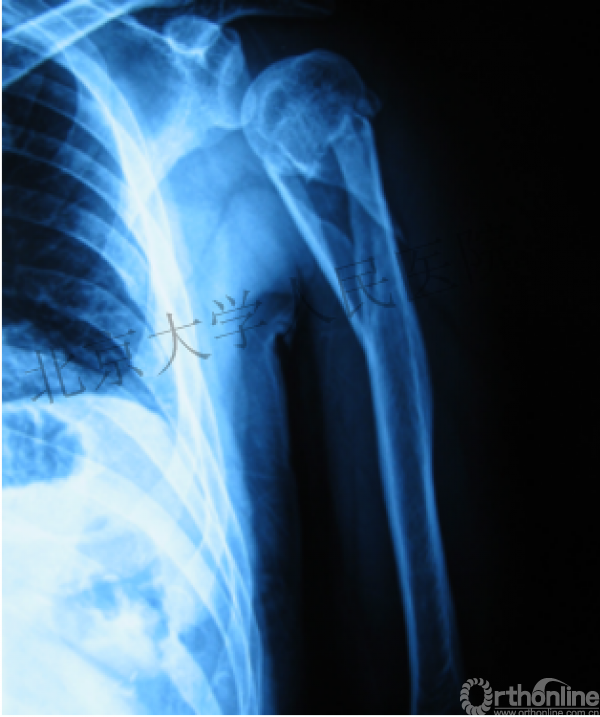

X射线照射后

10天后

值得吗?